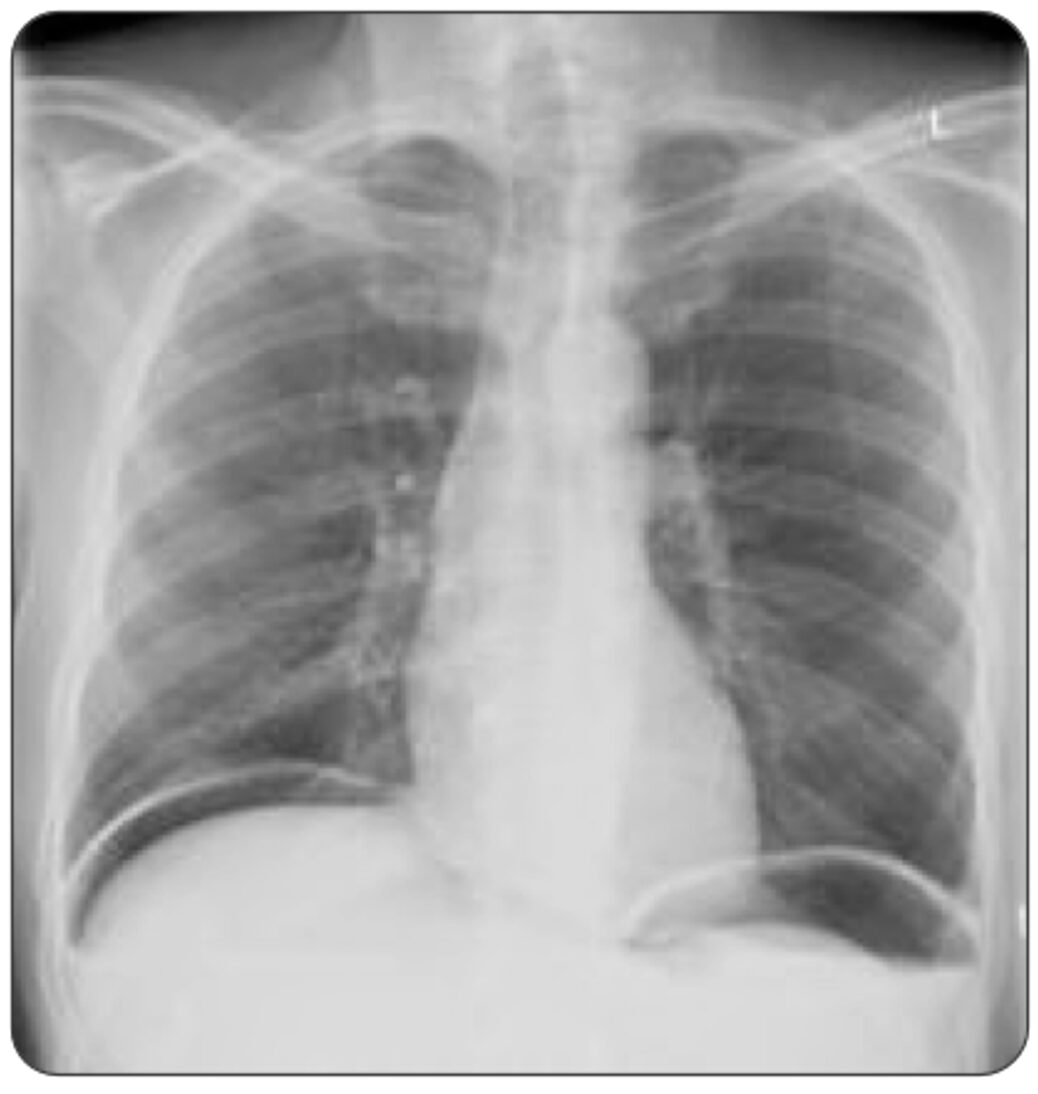

Chest X-Ray (CXR):

- Advantages of upright CXR:

- Can be done at the bedside for the unstable patient.

- Quick/convenient.

- Immediately available for review.

- Presence of pneumoperitoneum is diagnostic for a perforated viscus in 85-90% of cases.23,24

- Limitations:

- Variable sensitivity:

- Only 50-70% of hollow visceral perforations present with the characteristic ‘air under the diaphragm’ on an upright CXR, dropping as low as 20% in some studies.23,24

- Diagnostic utility is significantly limited by technique/positioning.

- Does not indicate the location of the perforation.23

Figure 1. Free air under the right hemidiaphragm on upright CXR, caused by bowel perforation. Source: Kulkarni R, Bowel perforation – subdiaphragmatic free gas. Case study, Radiopaedia.org (Accessed on 09 Nov 2025) https://doi.org/10.53347/rID-21444

A 55-year-old man with a history of peptic ulcer disease presents to the ED with sudden, severe abdominal pain that began abruptly around 12 hours ago. He describes the pain as intense and constant, radiating to his shoulders. He also reports feeling nauseated but has not vomited. On examination, he has significant abdominal tenderness with guarding and rigidity. His vital signs show mild tachycardia. His X-ray is shown above. What is the most appropriate next step?

This patient’s presentation, including the acute onset of severe abdominal pain, radiating shoulder pain, abdominal rigidity, and the presence of free air under the diaphragm on X-ray, strongly suggests perforated peptic ulcer disease (PUD), and the most appropriate next step in this scenario is surgical consultation.

Diagnosis of a perforated peptic ulcer is typically made with imaging. An upright chest or abdominal X-ray often reveals free air under the diaphragm, confirming the presence of a perforation. If the diagnosis is uncertain or if additional anatomical detail is needed, a CT scan of the abdomen can provide a more detailed view of the perforation and extent of intra-abdominal air and fluid. Laboratory tests may show leukocytosis and elevated inflammatory markers, though these findings are nonspecific. Serum amylase may be mildly elevated, especially in cases that involve gastric perforation.